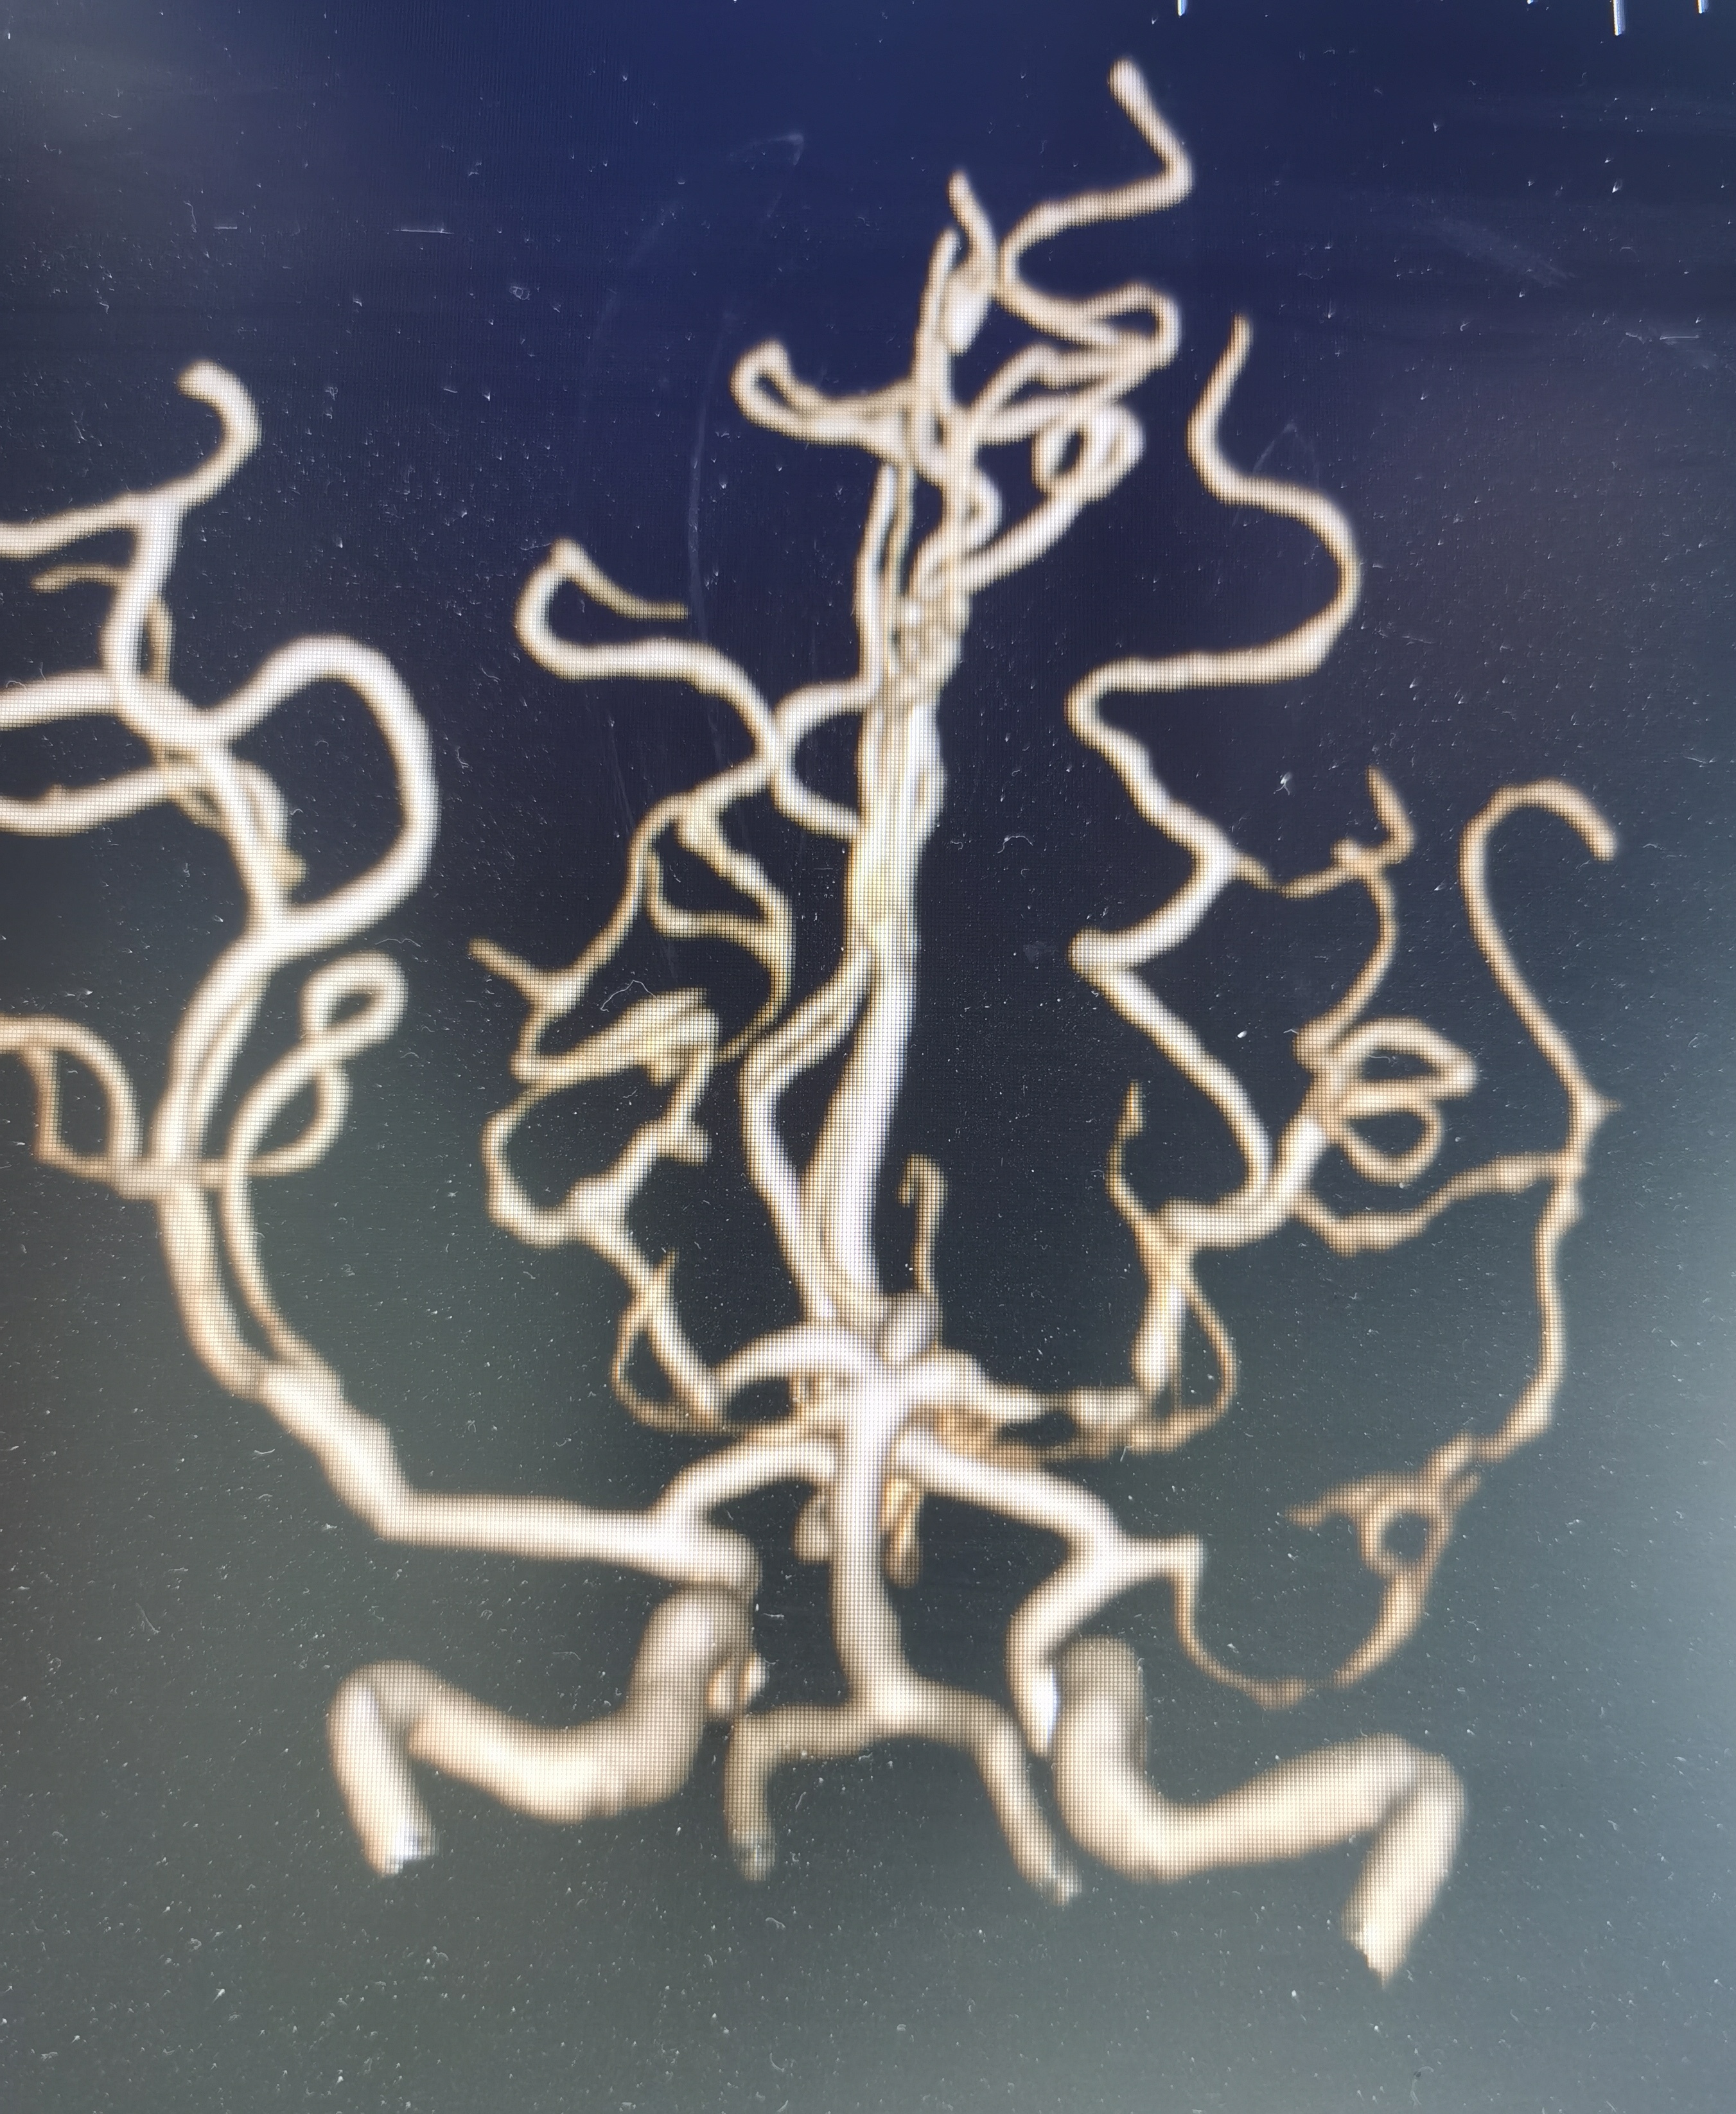

CTA示左侧大脑中动脉闭塞。